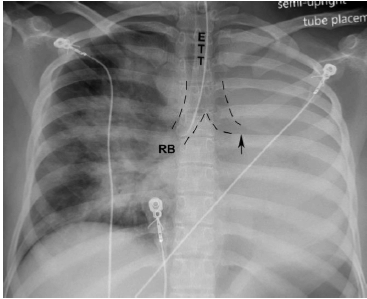

Qual o diagnóstico da radiografia de tórax ilustrada abaixo?

Enunciado 3288318-1